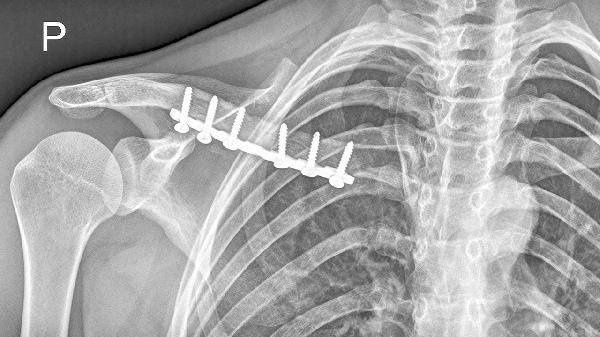

锁骨位置表浅,遭受直接暴力撞击如车祸、重物砸伤时易发生骨折。高处坠落或滑倒时手臂外展撑地,外力经肩关节传导至锁骨中段也可导致骨折。此类骨折多为横行或粉碎性,需通过X线检查确诊,急性期需用锁骨带固定4-6周,严重移位时需手术复位内固定。

乳腺癌、肺癌等恶性肿瘤转移至锁骨可能导致溶骨性破坏,轻微外力即引发病理性骨折。患者常伴有夜间痛、消瘦等症状,需通过CT引导穿刺活检确诊。治疗需针对原发肿瘤进行放化疗,骨折部位可采用髓内钉或钢板稳定。